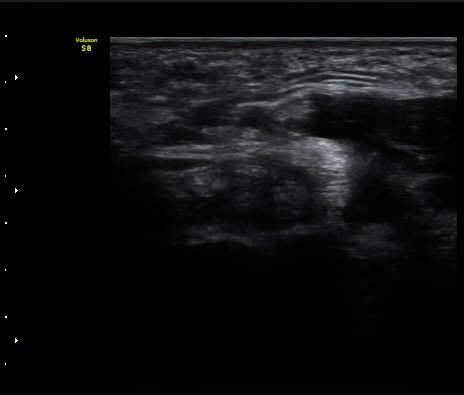

ÃÊÀ½ÆÄ °Ë»ç